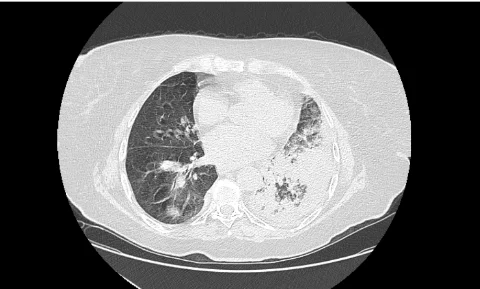

___В декабре 2024 года в пульмонологическое отделение по линии скорой медицинской помощи доставлена пациентка Б., 87 лет, с жалобами на боли в грудной клетке при дыхании, общую слабость. Заболевшей себя считает 6 дней назад, когда впервые появились боли в груди. По этому поводу принимала нестероидные противовоспалительные препараты. Обращает на себя внимание, что 4 дня назад выписана из другого стационара, где проходила лечение по поводу внебольничной двусторонней пневмонии. Госпитализирована в отделение пульмонологии с диагнозом «пневмония». На фоне стартовой терапии пациентка прошла с отрицательной динамикой. Основная причина ухудшения – пароксизм фибрилляции предсердий с развитием церебральной и сердечно-сосудистой недостаточности. В этой связи переведена в отделение анестезиологии и реанимации, где потребовалось протезирование дыхательной функции на фоне нестабильной гемодинамики. Путем объемного экстренного дообследования исключена тромбоэмболия легочной артерии. Больная погружена в медикаментозный сон, переведена на ИВЛ. Обследована, пароксизм фибрилляции купирован. Однако к этому моменту правое легкое было поражено на 100%, а в левом имелись выраженные очаги повреждения.

___Источник инфекции – бактерии, устойчивые к обычным антибиотикам. Параметры ИВЛ на момент старта лечения установлены «жесткие». Лечение в реанимации включало как поддержание медикаментозного сна и ИВЛ, так и вазопрессорную поддержку, антибактериальную, антигрибковую терапии, коррекцию водно-электролитных нарушений, профилактику острых стрессовых язв, зондовое питание, мероприятия общего ухода. Больной выполнены операции по катетеризации центральных вен, установлена трахеостома. Общий прогноз с учетом возраста, основной и сопутствующей кардиальной патологии крайне сложный.

___Вместе с тем, постепенно состояние пациентки удалось относительно стабилизировать. В течение 2х недель параметры вентиляции несколько смягчились. Однако степень повреждения была такова, что полный отказ от ИВЛ был по-прежнему невозможен.